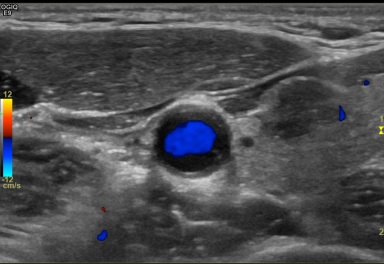

상기환자  외부 건진상 이상소견 세침검사위해 내원하신 50대초반 여성분으로 의심스러운 갑상선 좌엽 결절 세포검사진행후 갑상선암으로 진단되었습니다